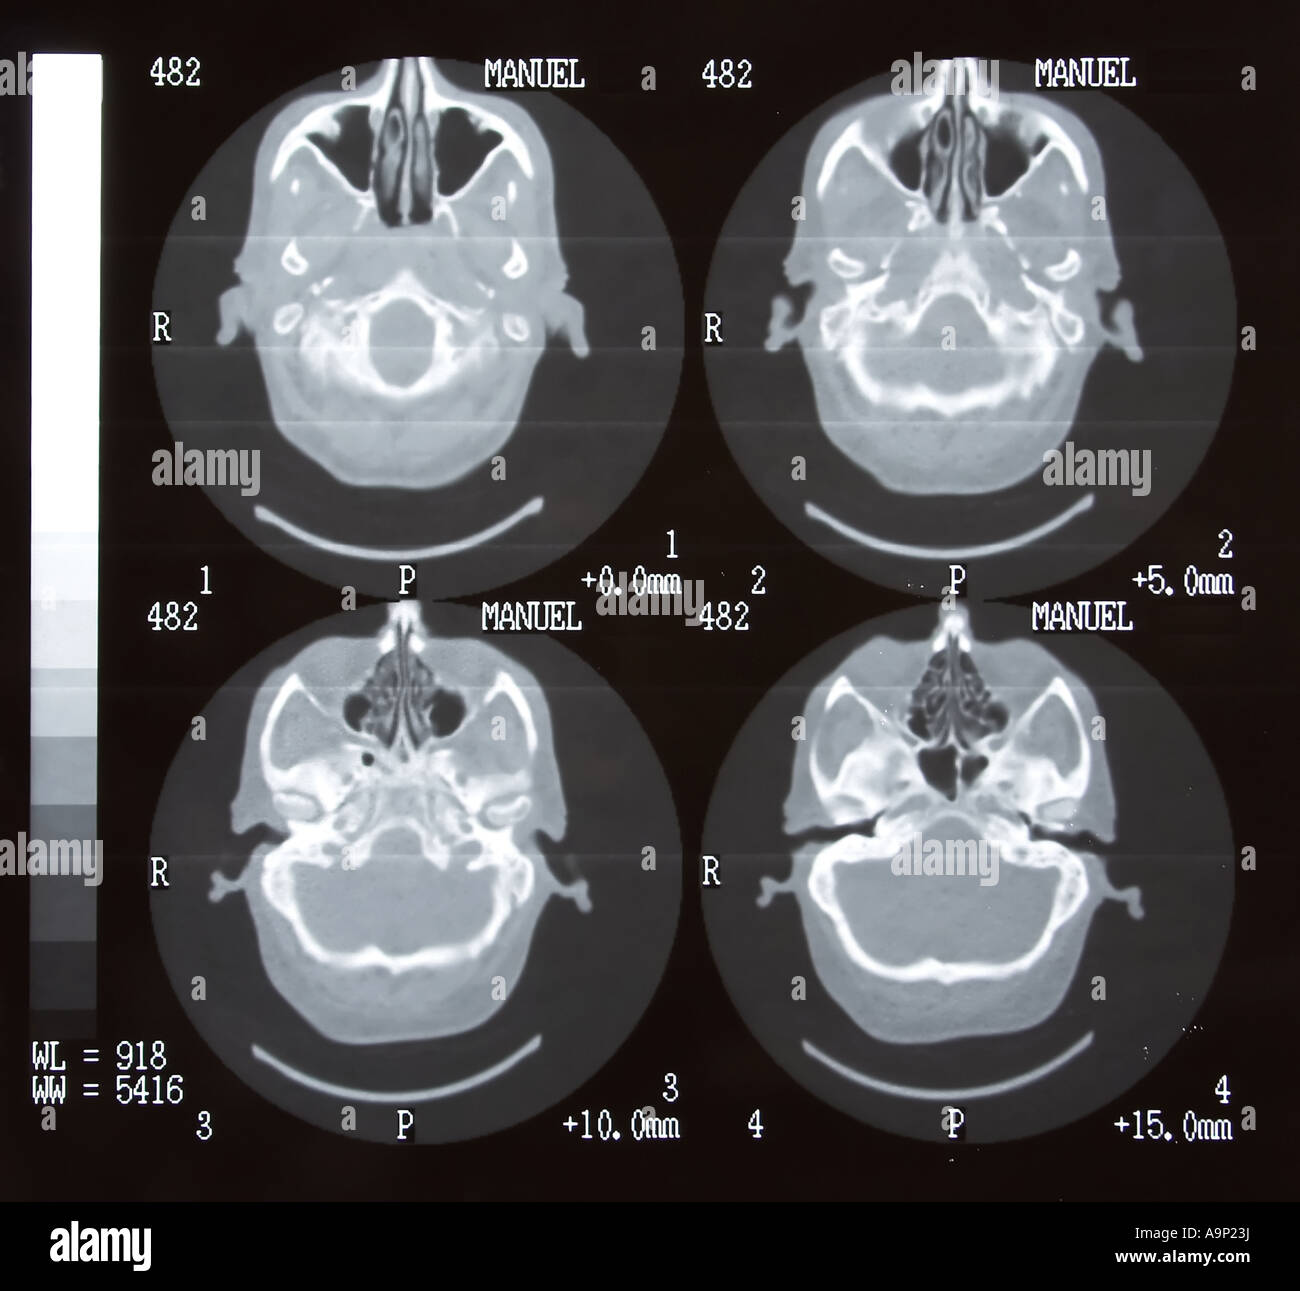

Tomodensitométrie cérébrale Banque D'Imageshttps://www.alamyimages.fr/image-license-details/?v=1https://www.alamyimages.fr/photo-image-tomodensitometrie-cerebrale-12412997.html

Tomodensitométrie cérébrale Banque D'Imageshttps://www.alamyimages.fr/image-license-details/?v=1https://www.alamyimages.fr/photo-image-tomodensitometrie-cerebrale-12412997.htmlRFA9P23J–Tomodensitométrie cérébrale